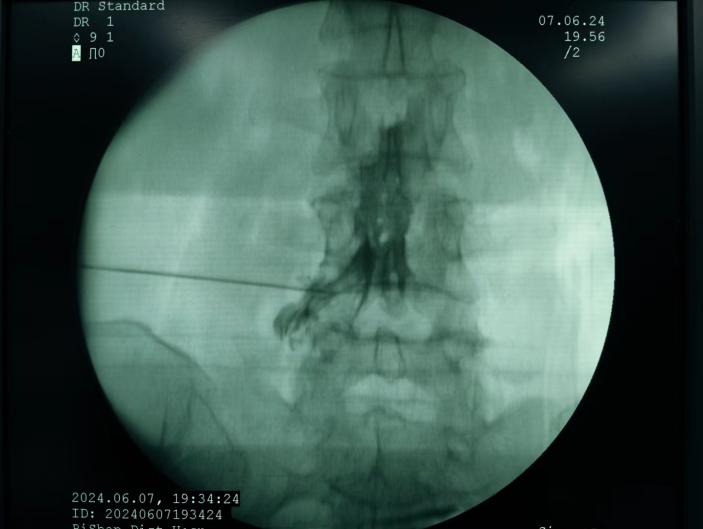

射頻消融治療,連續射頻或脈沖射頻對椎間盤或神經進行干預治療,目的是減小神經根周圍的壓力及對神經的調控治療,從而達到緩解癥狀的效果;

膠原酶椎間盤化學溶解術,是在影像引導下(C型臂X線機或CT),將膠原酶準確地注射到突出的椎間盤內及其周圍,使突出的椎間盤溶解并吸收,解除其對神經根的壓迫,進而緩解癥狀。